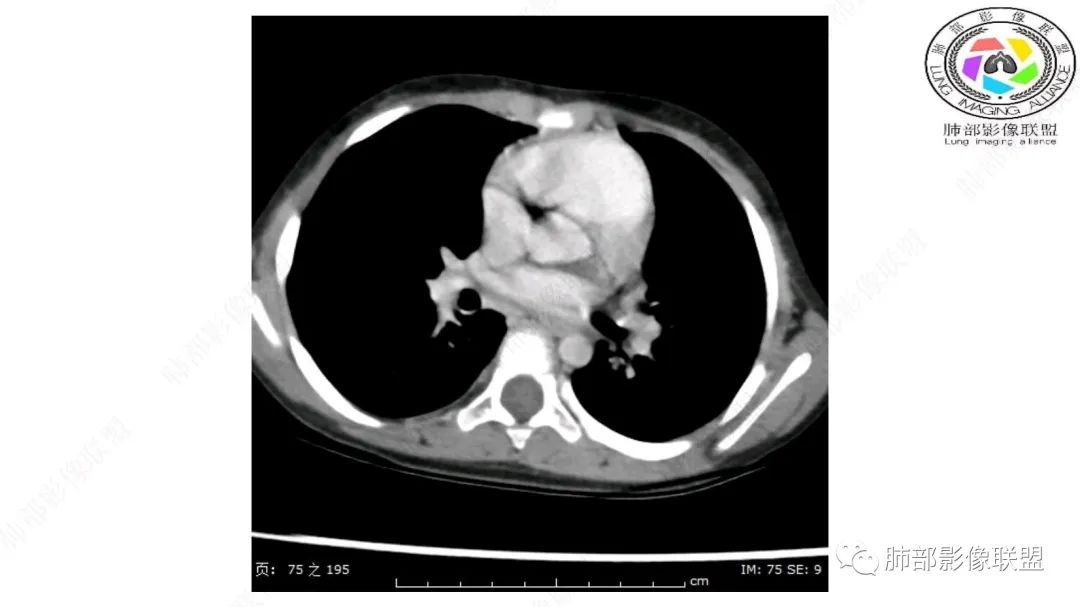

右上纵隔混杂密度肿块,边缘光整,与纵隔分界清,其内多发脂肪密度,增强无明显强化,其内血管穿行,考虑纵隔脂肪母细胞瘤,鉴别畸胎瘤,脂肪肉瘤。

右纵隔团状,密度不均,脂肪密度为主,内可见腺体样组织,类似乳腺,病灶边缘有分叶,与胸腺关系密切,增强后血管穿行。考虑胸腺脂肪瘤(不典型垂乳征),鉴别畸胎瘤。

可以看到造影剂进入的丛状结构

密度不均,非纯脂肪成分。斑片状密度略高区域有轻度填充式强化。

婴幼儿,病变较大,跨肺门,分叶,富含纤维或黏液、含成熟脂肪,破坏力弱或无,浸润性生长模式不明显,未见远处转移。

综合:富含成熟脂肪的、可以有丛状结构的,可以有纤维或黏液的良性或低度恶性肿瘤。常见疾病谱:脂肪瘤、神经纤维瘤样错构瘤、冬眠瘤、血管脂肪瘤、髓脂肪瘤、脂肪母细胞瘤、黏液样脂肪肉瘤。

病灶属于交界区,主体位于肺内,占位效应明显,前方突入胸壁,胸腺受压变形,胸膜显示欠清楚;病灶包绕上叶肺动脉;似乎有体动脉供血。符合肺内的点:包绕上叶肺动脉分支;符合纵隔的点:前方似乎突入胸壁,与胸腺关系比较密切,但是与上腔静脉的关系提示病灶不支持纵隔来源,前纵隔的常规会将上腔静脉受压后移、外移,这是不符合的。

内部血管明显,部分病灶密度增高,单纯脂肪瘤不支持。可惜的是:没有提供CT值:是否强化?如果强化,警惕恶性;胸腺肯定不符合,胸腺会将上腔静脉朝后推移。